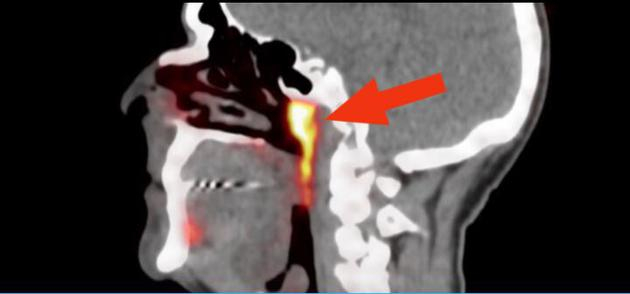

在仔细读取一组扫描图时,研究人员注意到头部有两个很不寻常的结构。这是两个扁平、细长的腺体,长约4厘米,不显眼地挂在连接耳朵和喉咙的管状结构上。研究人员对这些图像感到十分困惑。他们首先查看了100份历史上的扫描图像,还对两具尸体进行组织解剖,发现这些腺体与位于舌头下方的已知唾液腺有相似之处。这些新腺体还连接着较大的引流管,可能暗示着它们正在将液体从一个地方输送到另一个地方。

根据这组腺体所处的位置,研究人员将其命名为“咽鼓管腺”(tubarial glands),因为腺体十分靠近咽鼓管圆枕(torus tubarius)

我们尚不完全清楚这些腺体是如何逃脱解剖学家的“法眼”。不过,研究作者之一、荷兰癌症研究所的放射肿瘤学家沃特·沃格尔说:“这个位置并不容易进入,你需要非常灵敏的成像技术才能检测到它。”人体其他较大的唾液腺通常靠近皮肤表面,可以很容易通过解剖发现,但新的这组唾液腺隐藏在头骨底部,就不那么容易找到了。根据这组腺体所处的位置,研究人员将其命名为“咽鼓管腺”(tubarial glands),因为腺体十分靠近咽鼓管圆枕(torus tubarius)。

在这项研究中使用的扫描成像技术被称为PSMA PET/CT(正电子发射体层摄影术/计算机体层摄影术),也被专门用于确定这些患者中肿瘤的生长。研究人员称,只有更新的PSMA-PET/CT成像技术才能检测到这些唾液腺的结构,这超出了超声波、CT和核磁共振(MRI)扫描等技术的可视化能力。